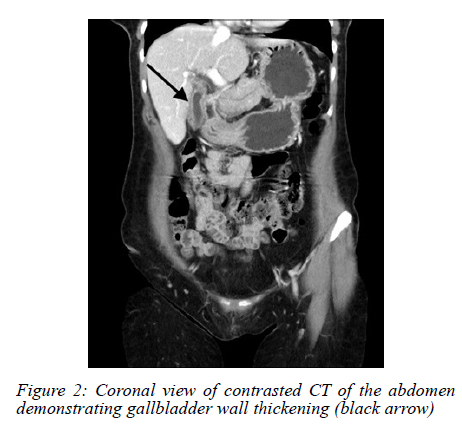

An abdominal ultrasound (AUS) showed a possible stone in the gallbladder neck, with a thickened and oedematous gallbladder wall (Figure 1). No masses were noted on sonar. The history of loss of weight was further investigated. A colonoscopy was performed, which was normal. A computed tomography (CT) scan did not show any concerning features, and a thickened gallbladder wall was once again visualised (Figure 2, 3).

Radiologically, CT and ultrasound findings are nonspecific, ranging from wall thickening to mass-like lesions with necrosis or calcification.68 These features overlap significantly with gallbladder malignancy or chronic inflammation,6,8 making preoperative diagnosis challenging. Radiologic "red flags" suggesting TB over carcinoma include gallbladder wall with necrotic core, multiple flecked calcifications, broad-based micronodular lesions, pericholecystic oedema, and necrotic lymph nodes.6 Consequently, in the absence of systemic TB features or pulmonary symptoms, most diagnoses hinge on postoperative histopathology, where necrotising granulomas with or without acid-fast bacilli confirm the diagnosis.9